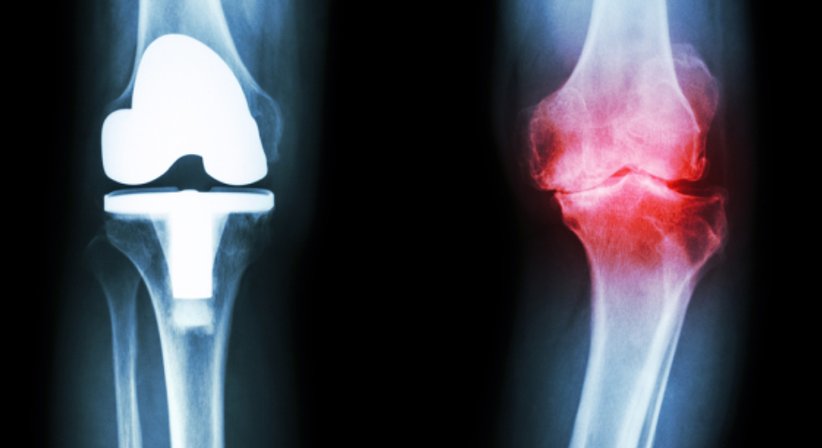

Die Implantation von Knieprothesen zählt zu den häufigsten Eingriffen im Bereich der orthopädischen Chirurgie. Es handelt sich um eine Operation, bei welcher die zerstörte Knorpeloberfläche des Kniegelenks entfernt und durch entsprechende Metall- und Kunststoffkomponenten ersetzt werden.

Bei Knieprothesen kann zwischen zwei verschiedenen Ersatzmöglichkeiten unterschieden werden, dem partiellen Kniegelenksersatz und dem totalen Kniegelenksersatz. Ein partieller Kniegelenksersatz kommt bei Patienten in Frage, bei welchen die Bänder am Kniegelenk noch erhalten und voll funktionsfähig sind und nur ein Teil vom Kniegelenk abgenutzt ist. In solchen Fällen wird nur der abgenutzte Teil vom Knie erneuert. Bei einem totalen Kniegelenksersatz werden hingegen alle Gelenkanteile durch künstliche Elemente ersetzt.